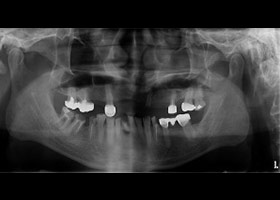

病患:55歲先生。

主訴:多顆缺牙,想全口治療。

多顆缺牙、牙周病、多顆蛀牙。

治療前

多顆缺牙及牙周病、蛀牙

proimages/Case/dentalimplant/10/02/before01.jpg